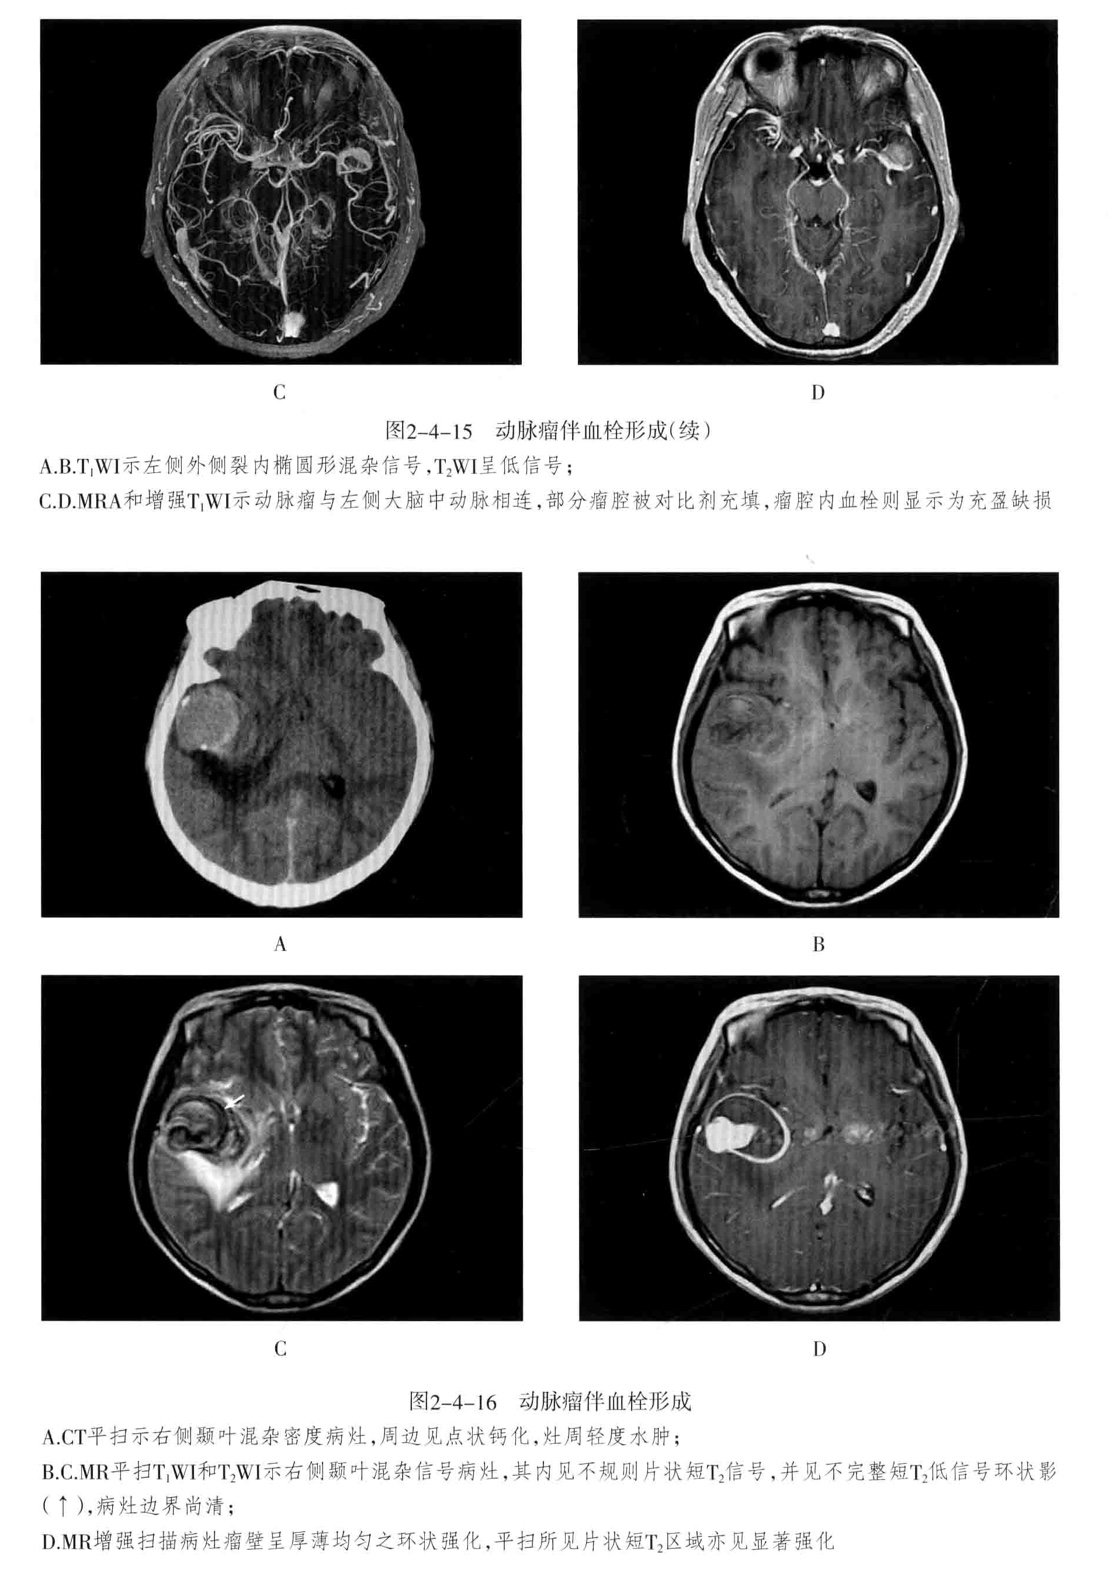

三、颅内动脉瘤

定义:颅内动脉局灶性异常扩大。

- CT平扫为圆形高密度影,边缘清楚、增强有均匀强化,CTA或MRA可明确显示动脉瘤及其与载瘤动脉的关系。瘤样凸起。

- 动脉瘤的瘤腔在T1WI、T2WI上均呈低信号,动脉瘤内有涡流时,也可产生轻微的不均质信号;瘤内血栓显示为高低相间的混杂信号。